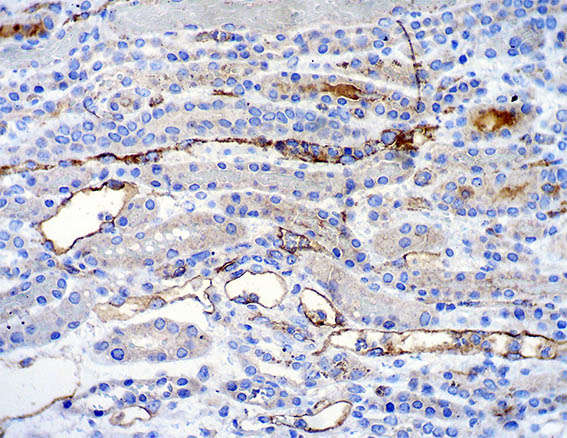

Figure 12. Immunohistochemistry for C4d (paraffin-emdedded tissue), X400.

Immunofluorescence for IgA, IgG, IgM, C3 and C1q: Negative.